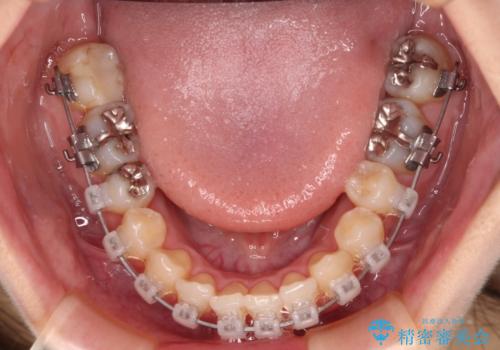

- クリアブラケット

- 1年11ヶ月

下顎歯列の叢生は軽度であることと、口元の突出感が全くなかったことから、八重歯解消のために上顎左右第一小臼歯を抜歯し、ワイヤー装置にて矯正治療を行うこととしました。

八重歯をスムーズに解消するために、補助装置を用いることで速やかに歯列を整えることができました。